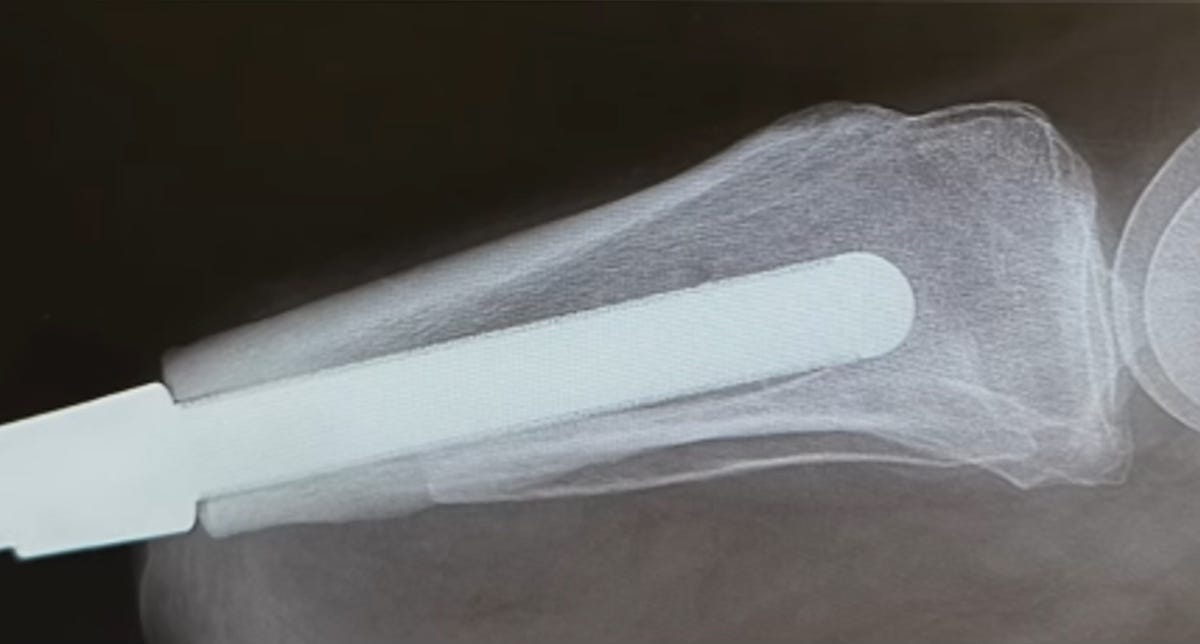

Example: A bone-anchor implant manufactured to suit a particular limb-loss patient identified by a surgeon will perfectly fit that patient, following the length and curvature of that patient’s (remaining) bone. The implant is unique to the patient and fits that patient alone.

These two uses of additive manufacturing go together. Patient-matched design enables a fit that serves osseointegration, because the tailor-made form of the device helps maximize contact between bone surface and implant surface. Meanwhile, the patient-specific device generally needs osseointegration, relying on this for fixation. The departure from a standard design means departing from established connection points for standard fasteners such as screws through a titanium rod. For the orthopedic implant that has been suited to the patient’s bone, the patient’s bone itself is the best and potentially essential means of affixing the device.